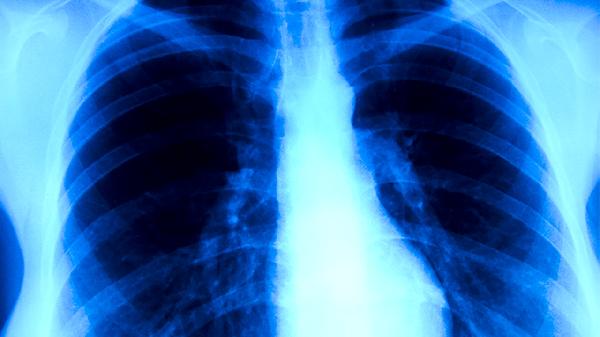

5-15岁群体因免疫系统发育不完善,成为高发人群。学校等集体环境加速传播,临床常见班级聚集性病例。患儿多表现为顽固性干咳伴中低热,肺部体征不明显但胸片显示斑片影,需及时进行血清抗体检测确诊。